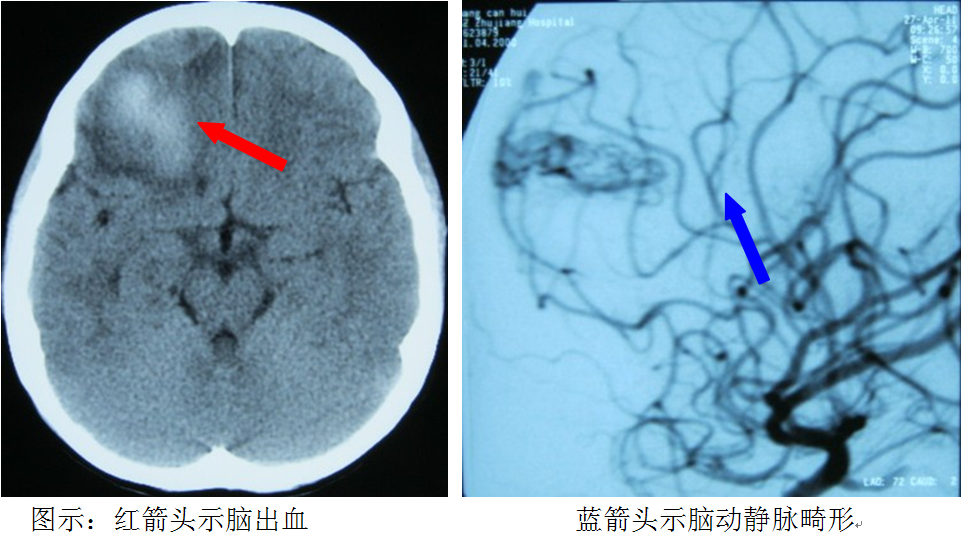

腦動靜脈畸形簡介

腦動靜脈畸形是一種常見的腦血管性疾病,是胎兒期腦血管形成異常的先天性疾患,呈家族性的少見。發(fā)病平均年齡約25歲左右,男性發(fā)病率大于女性。

腦動靜脈畸形最常見危險是腦出血,約占52%-77%,半數以上在16-35歲之間發(fā)病。出血與季節(jié)無關,通常發(fā)生在正?;顒訒r,懷孕期間的出血危險增加。出血前數周至數年內可出現頭痛、癲癇(俗稱羊癲瘋)發(fā)作和一些局灶性神經功能障礙樣癥狀。未出血的腦動靜脈畸形患者可單獨表現癲癇發(fā)作、長期的頭痛、感覺障礙等神經功能障礙樣癥狀。還有部分腦動靜脈畸形可無任何臨床癥狀,或體檢時發(fā)現或終身不發(fā)病。

腦血管的CTA,或頭顱的MR,或腦血管的DSA檢查,可以確斷腦動靜脈畸形。因腦動靜脈畸形發(fā)生腦出血的機率高,且腦出血的致殘及致死率高,故當發(fā)現腦動靜脈畸形時,大多數患者均需要進行積極的治療,特別是少年及青壯年患者。目前有開顱手術切除、血管內介入治療及放射學的3種治療方案,其治療方案的選擇因人而異和因病而異。大部分腦動靜脈畸形患者預后良好,治療后發(fā)生腦出血的風險明顯降低。(神經外科 龍青山)